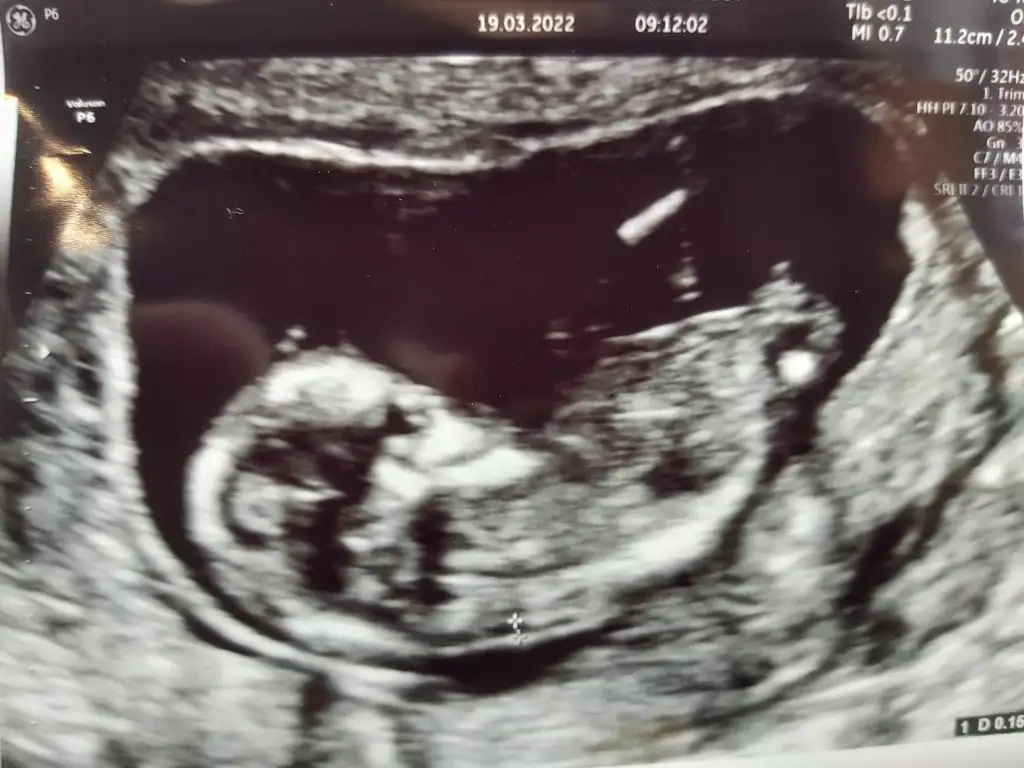

Kızlar bugün kontrolüm vardı herşey yolundaymış çok şükür ense kalınlığı burnu hepsi normal çıktı. Herkesinkine bir yorumum oluyordu kendi bebeminkine bişey diyemiyorum😅 Doktor erkeğe benzettim ama kızlarda da oluyor çıkıntı 16.haftada net söylerim dedi.

Günaydın kızlar mutlu haftasonlari olsun gene karlı ve soğuk bir hava bu sene yaz gelmeyecek sanırım tipe bakar mısınız çatık kaslı bir bebiş uygulamada 🥰 bir de diğer resime bakar mısınız canlar doktor bana kaba taslak 13 hafta dedi ama burda 14 hafta yazıyor karıştı herşey ya neye inanacagima şaşırdım resmen bilen birisi açıklayabilir mi

Sanki baş popo mesafe ölçümleri ile uyluk kemiği ölçümleri 14 hafta ile uyumlu gelmiş. Orda yazan o. 13 ne bilemedim tabi. Belki tüm ölçümleri toparlayınca çıkan ortalama hafta 13tür.